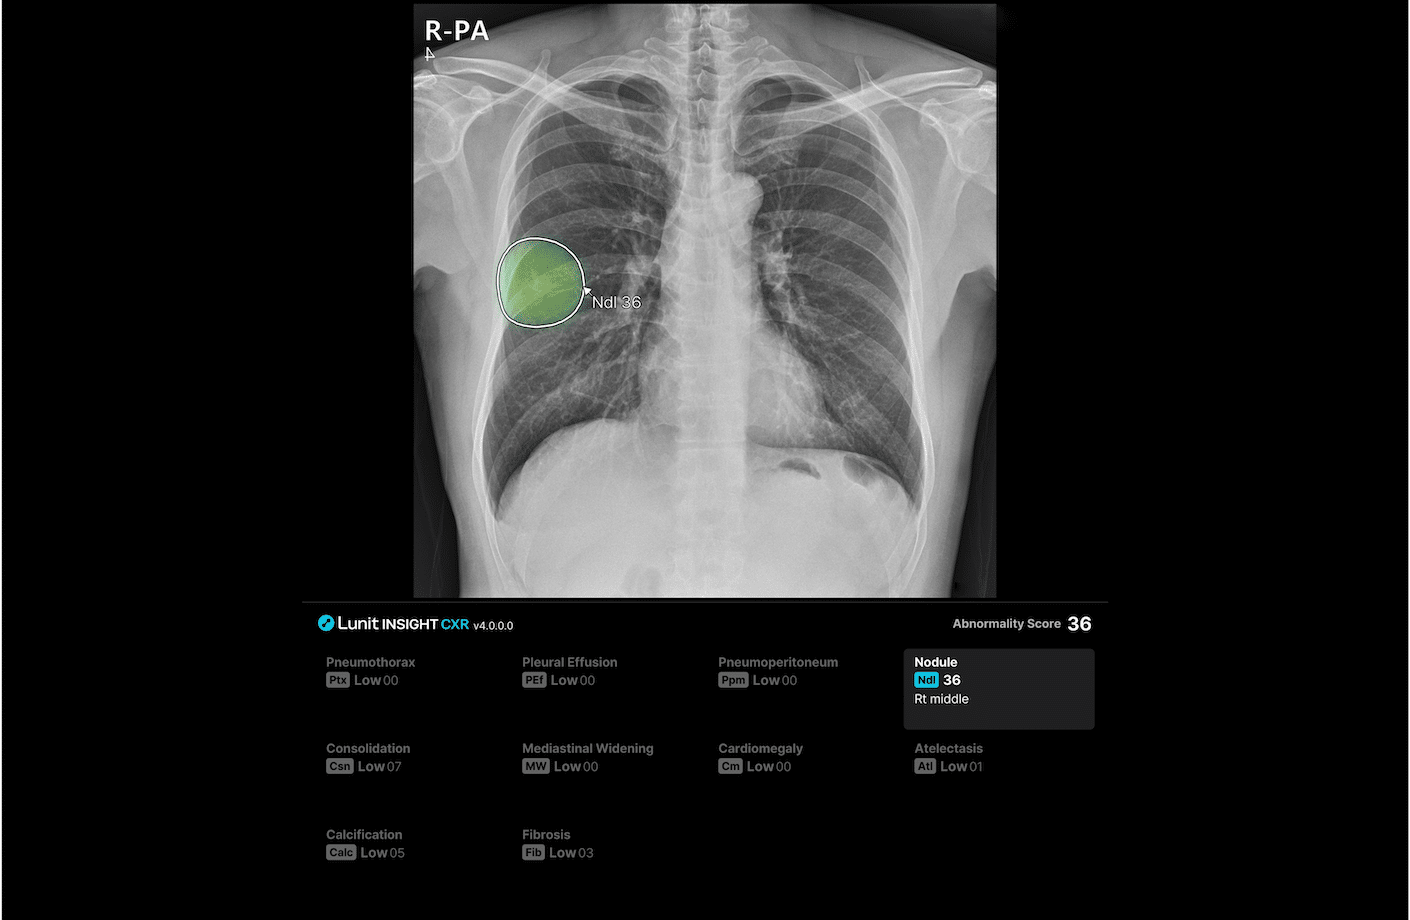

루닛 인사이트 CXR4는 결절, 경화, 기흉, 흉막삼출, 무기폐, 기복증, 심장비대, 종격동 확장, 석회화, 폐섬유화 등 흉부 엑스레이에서 가장 흔하게 발견되는 10가지 비정상 소견을 진단·검출 보조하며, 폐결핵 선별을 지원합니다.

루닛 인사이트 CXR4는 환자의 과거 영상을 자동으로 불러와 현재 영상과 비교해 이상 소견의 변화를 확인할 수 있도록 기호로 표시합니다. 결절의 진행 여부 뿐 아니라 기흉, 흉수, 경화 병변의 면적 변화 추적도 가능합니다.